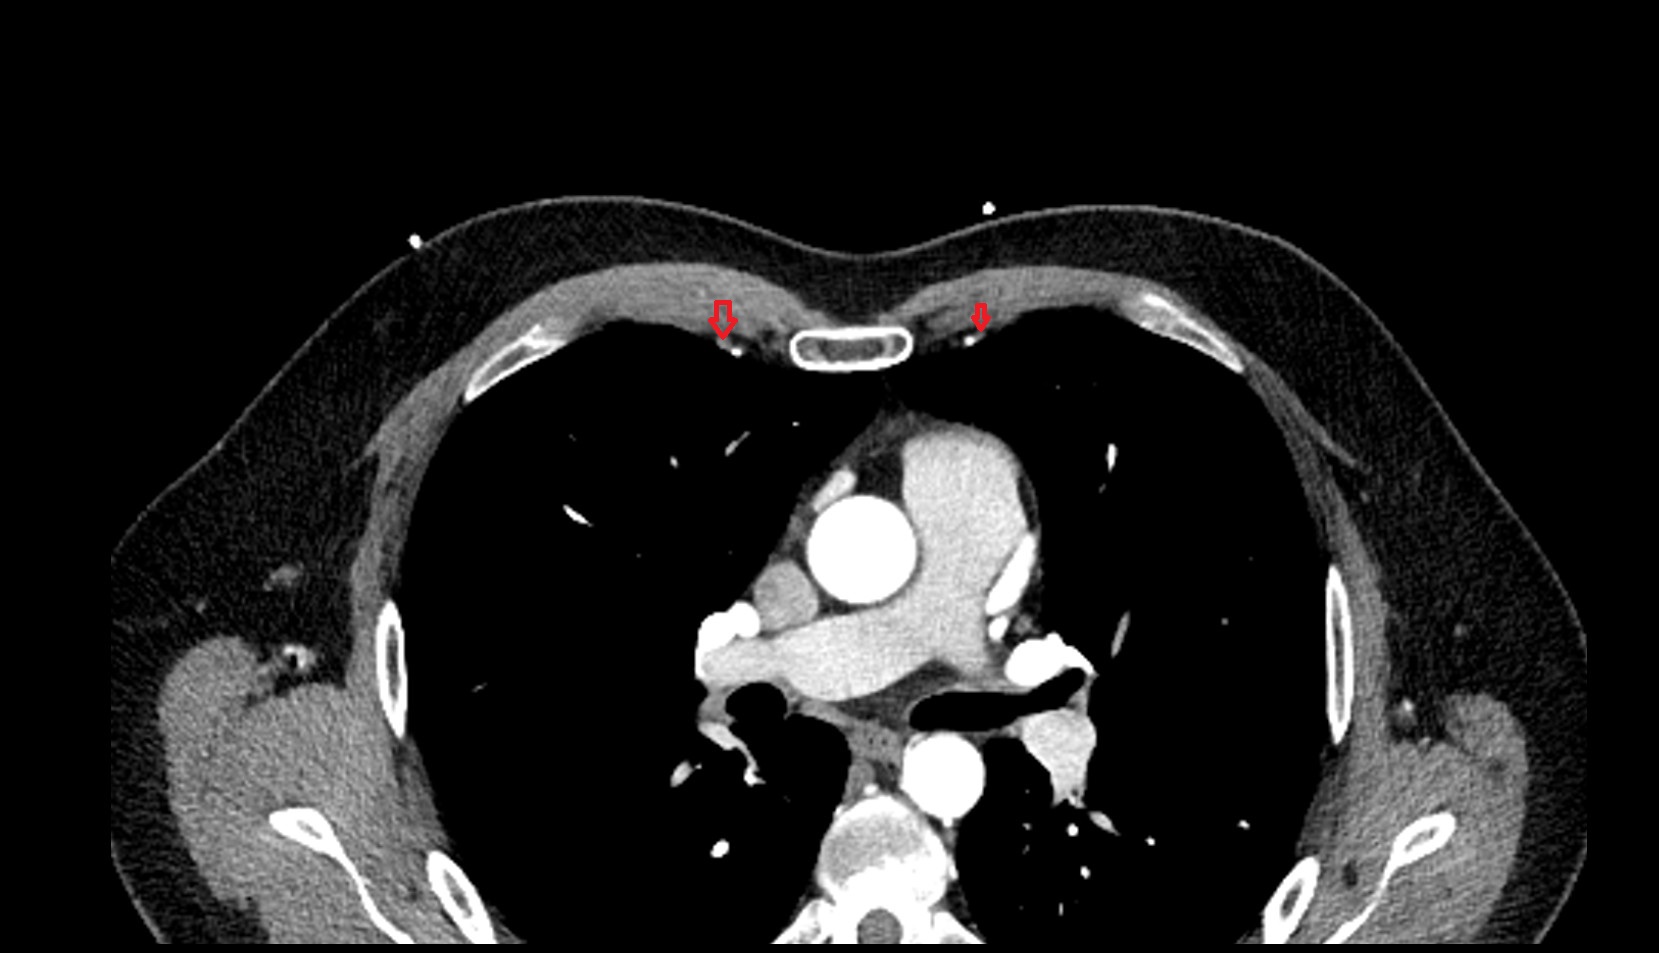

- Manubrium of sternum

- Sternocostal synchondrosis of first rib